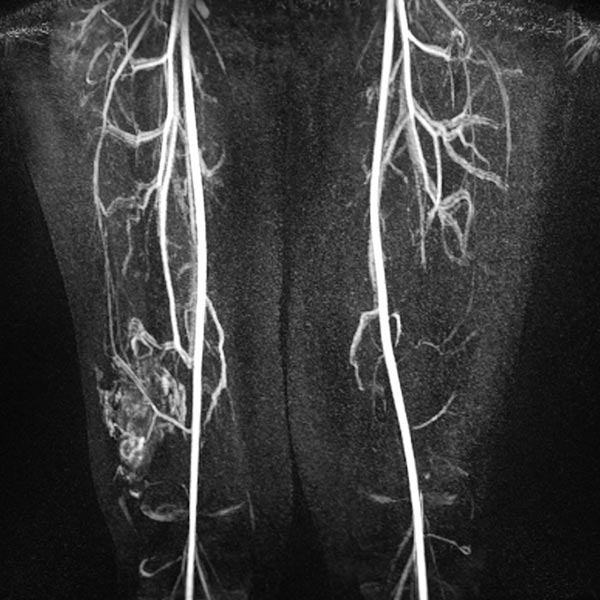

Die dynamische MR-Angiographie 62 s nach Injektion des Kontrastmittels zeigt ein langsames pooling des Kontrastmittels in der Läsion ohne frühen venösen Rückstrom (Slow-flow-Malformation). Die Läsion steht in Verbindung mit dem tiefen Leitvenensystem (Kommunikationsvenen).